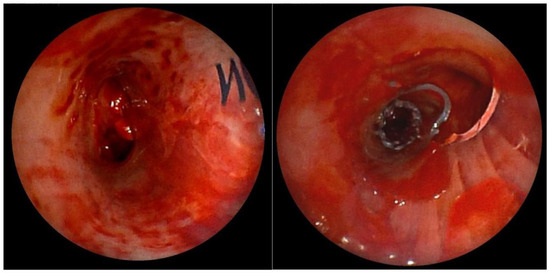

After mechanical disobliteration of tumor masses using a cryoprobe, it was possible to insert a Y stent. We adjusted the Dumon stent (16 × 30 × 30) according to the distance measurements using the LJ system (Figure 4). Subsequently, a “stent into stent” (Microtech t 12 × 20) was inserted into the right lower bronchus for torsional changes, twisting the distal part of the right arm of the original Dumon stent.

Figure 4. Left leg of the Dumon stent (left) and right arm of the stent with a cut-out hole for the upper lobar bronchus. In the distal part of the stent, a Microtech “stent into the stent” was inserted for torsional changes (right).